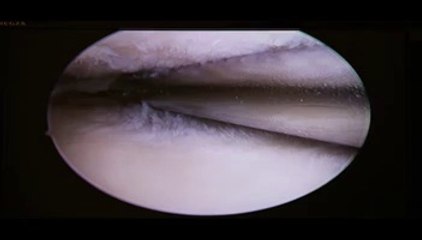

doctor ashfaq ahmed konchwala